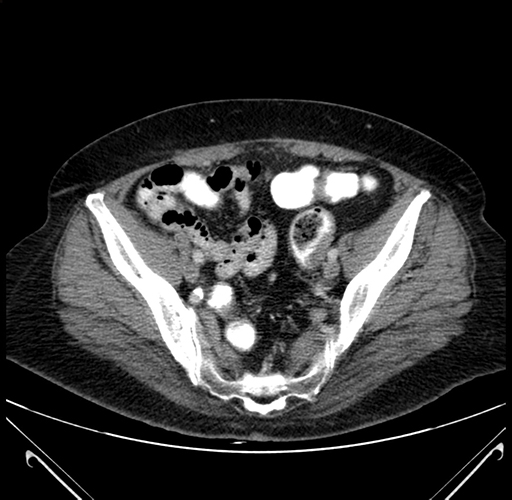

Pre-Chemo: Axial Venous

Axial Venous